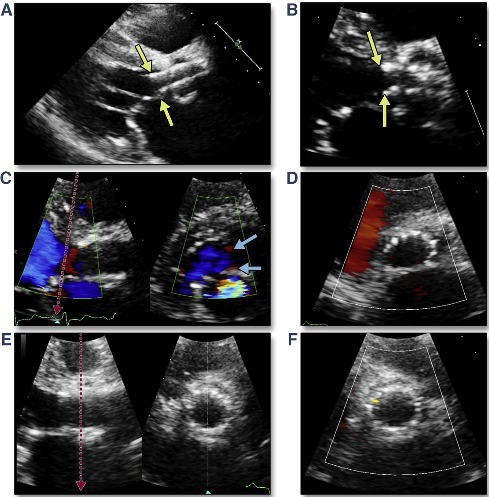

术前检查显示:超声提示主动脉瓣钙化并中重度狭窄、中度关闭不全,二、三尖瓣轻度关闭不全,左室增大,EF:55%。

超声提示:主动脉瓣钙化并中重度狭窄、中度关闭不全,二、三尖瓣轻度关闭不全,左室增大,EF:55%。

主动脉根部:功能型二叶瓣,瓣叶增厚,重度钙化,左右可见钙化融合。左冠开口高度约14mm,右冠开口高度约15.4mm。法式窦结构大,STJ高度约20.2mm、直径约30.6mm。升主动脉未见明显扩张,心脏角度约54°。左室大小尚可,心肌增厚。CT显示患者结构偏大,瓣环及流出道成敞口状。瓣上各辅助锚定区域处于临界值,给手术操作带来挑战。 请注意,我没有改变原文的意思。

功能型二叶瓣,瓣叶增厚,重度钙化,左右可见钙化融合,左冠开口高度约1 4mm,右冠开口高度约1 5.4mm,法式窦结构大,STJ高度约20.2mm、直径约30.6mm,升主动脉未见明显扩张,心脏角度约54°,左室大小尚可,心肌增厚。CT显示患者结构偏大,瓣环及流出道成敞口状,瓣上各辅助锚定区域处于临界值,给手术操作带来挑战

在瓣膜释放完成后,立刻进行了造影和超声评估。结果显示,患者跨瓣压差显著降低,超声检查没有发现瓣周漏,全主动脉和入路也没有出现并发症。手术圆满成功。